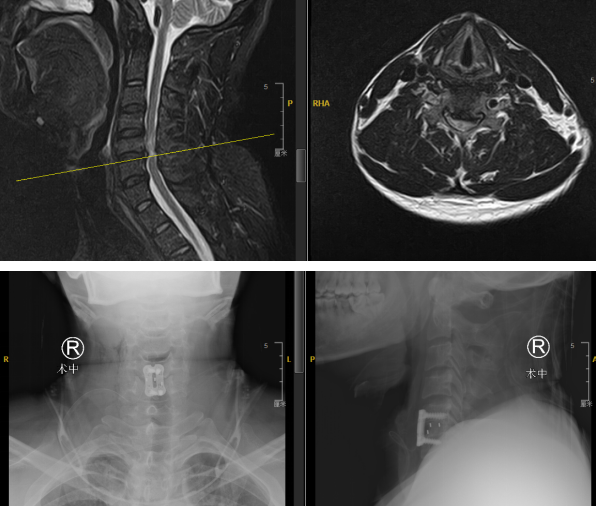

经过充分的术前准备,尚军主任、张冶、郭松医生组成的手术医生团队为孙某进行“颈椎前路减压+内固定+椎间融合术(C6/7)”。

术中

手术在骨科机器人定位下,切开约3cm切口,保障神经安全和手术的有效性,所有操作一步到位。术中,巧妙避开血管、神经,将椎间盘组织取出,显露脊髓硬膜,充分减压。使用超声骨刀打磨椎间隙,放置融合器及钢板螺钉固定。手术用时约1小时,出血量不超过10ml。